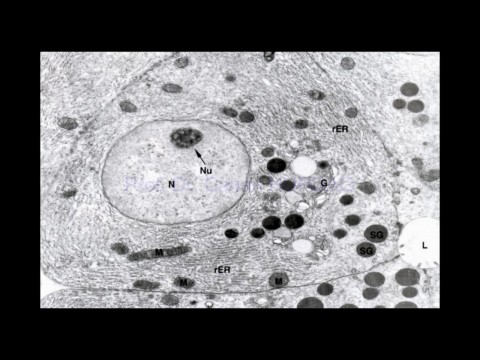

Page 4 - EPİDEL DOKU III

Prof. Dr. Canan HURDAG

27-Mar-20                                    Hücre çekirdek.Epitel Dokusu                                                    4